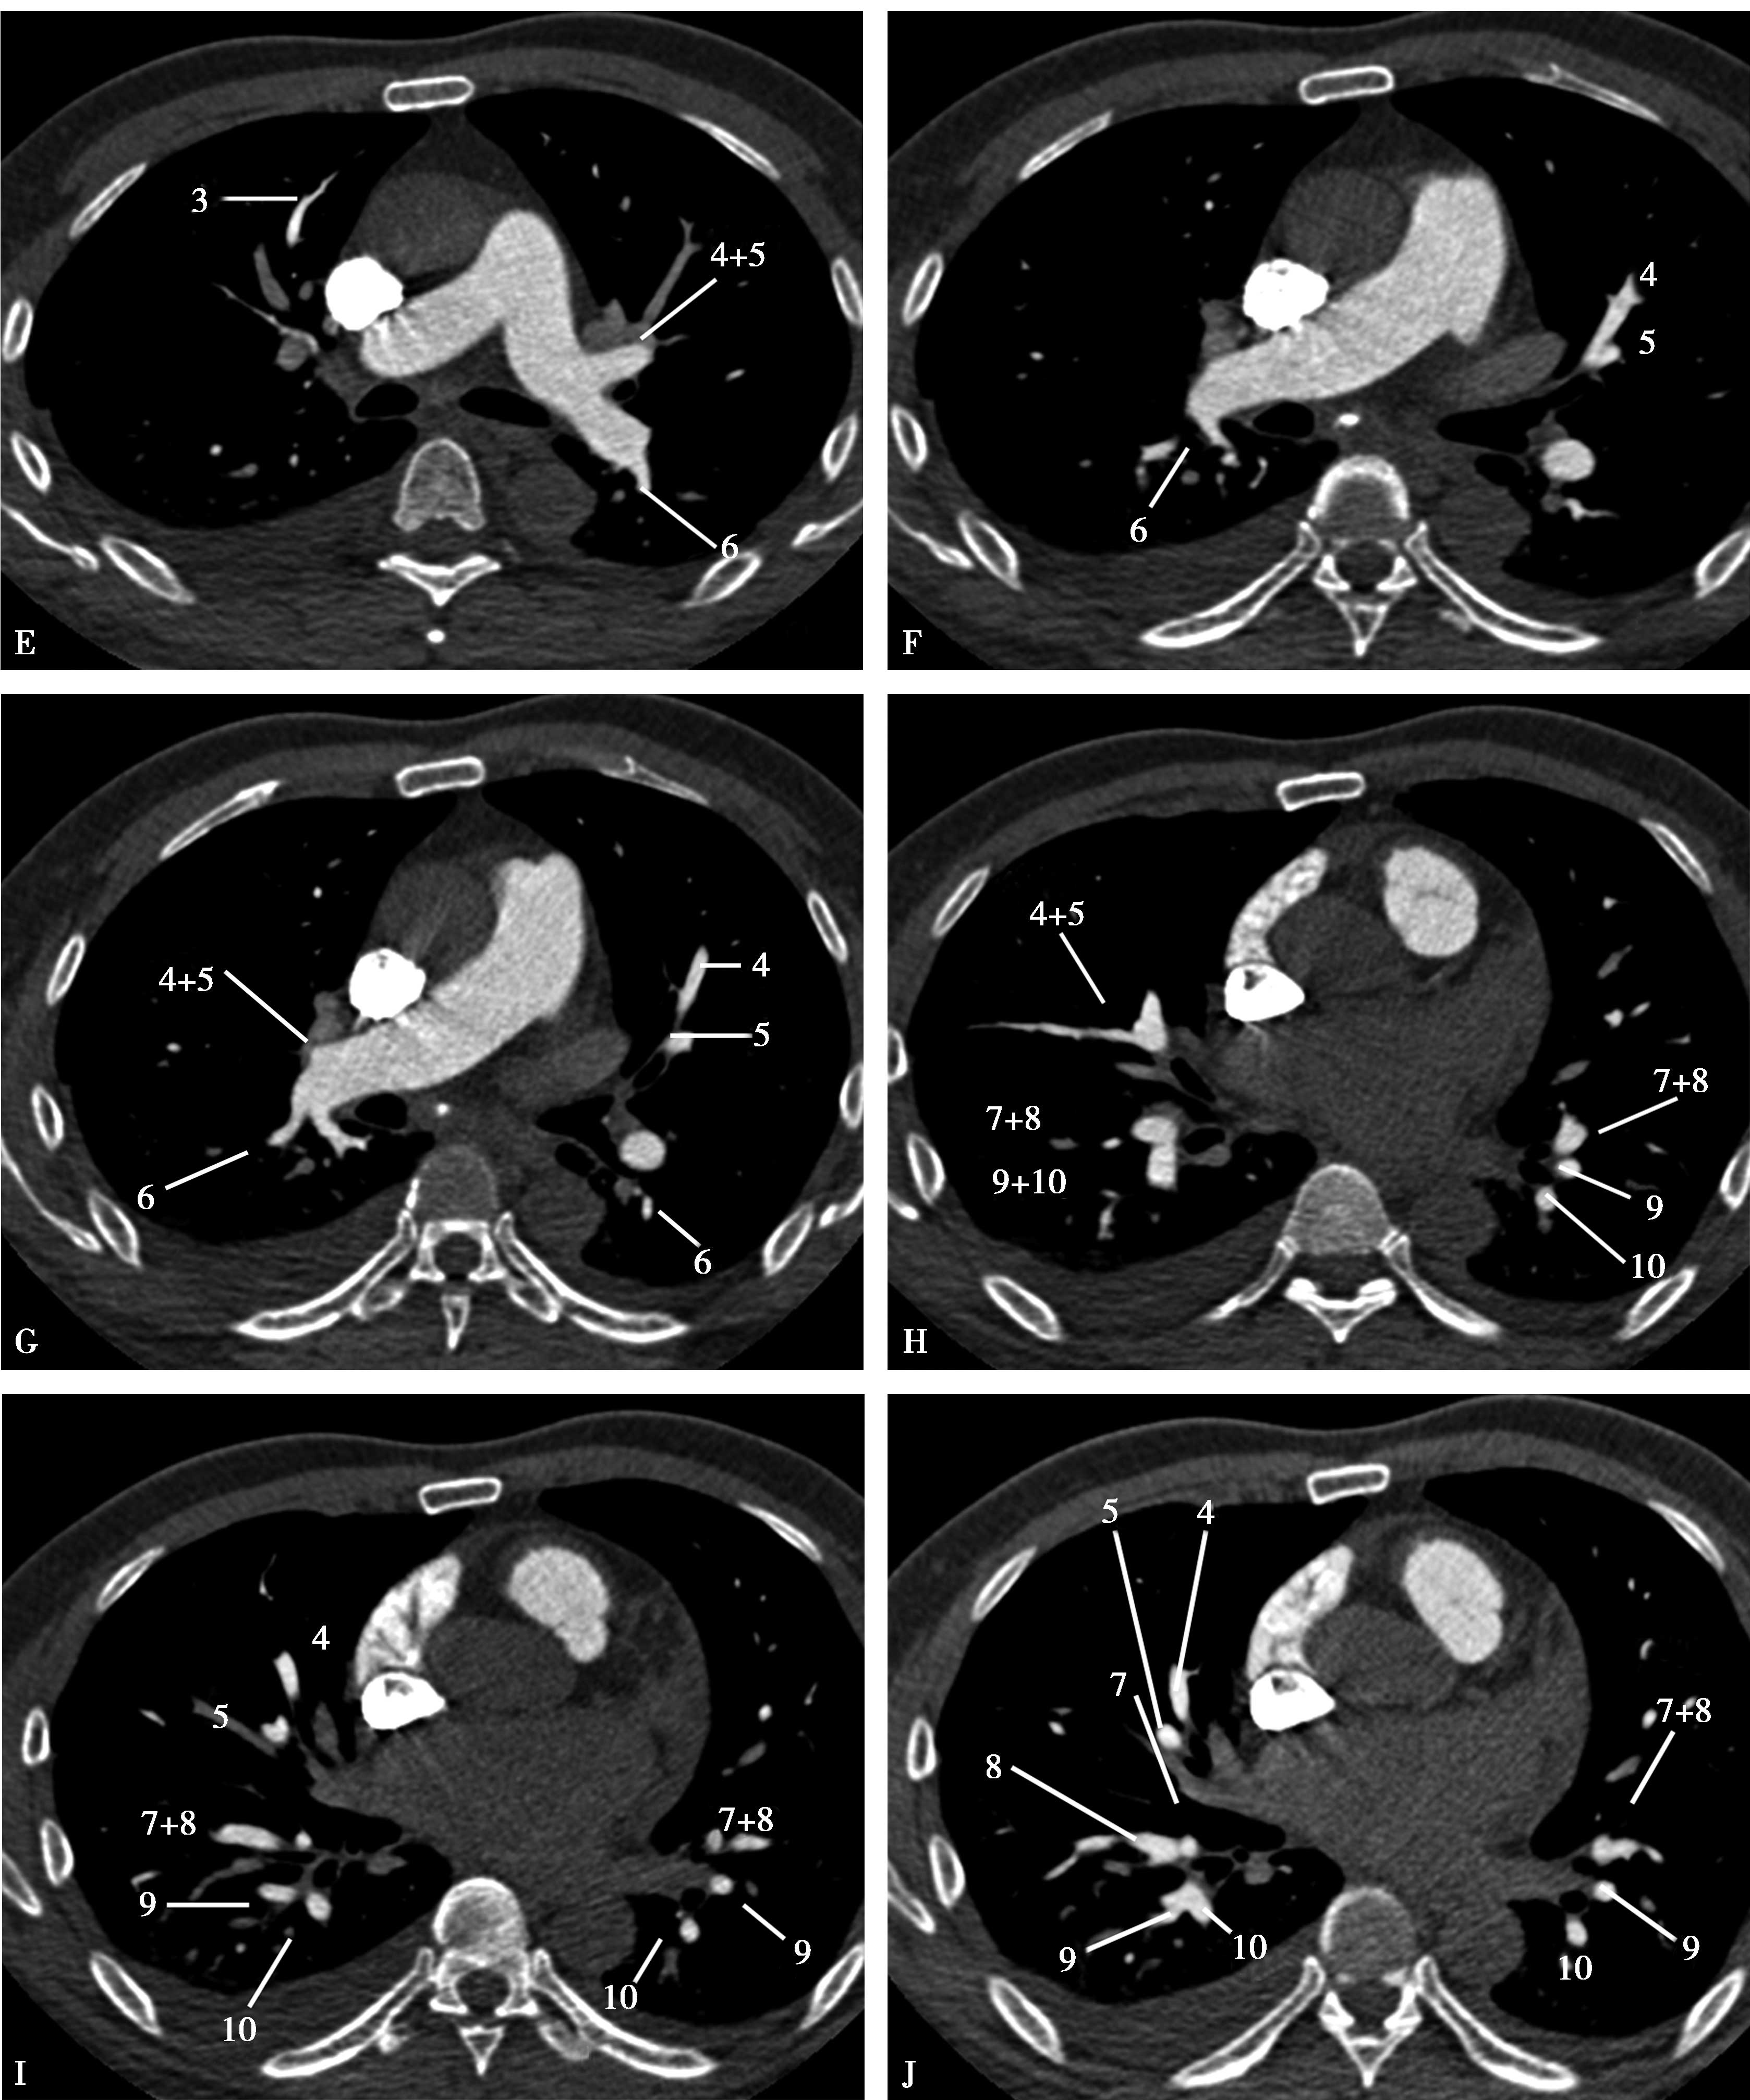

(一)肺动脉解剖(图8-2-6)

(1)上叶肺动脉层面(图8-2-7A~D)。

(2)中叶层面(图8-2-7E、 F)。

(3)中、下叶层面(图8-2-7G~J)。

图8-2-7 肺动脉横断扫描

A~D.上叶:1.尖段;2.后段;3.前段。E~J.(右肺)中叶:4.外侧段;5.内侧段。(左肺)舌叶:4.上舌段;5.下舌段。下叶:6.背段;7.内基底段;8.前基底段;9.外基底段;10.后基底段